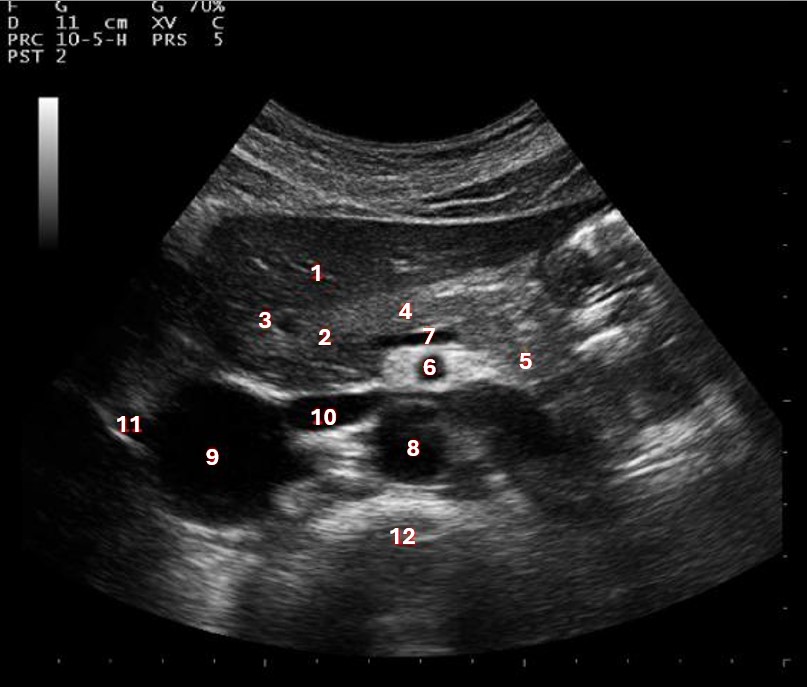

Which of the following structures is labeled #5?

lateral left lobe |

What lobe of the liver is indicated by #1?

posterior right lobe

What structure/vessel is indicated by #8?

medial left lobe |

What lobe of the liver is indicated by #2?

anterior right lobe |

Which of the following structures is labeled #1?

Which of the following structures is labeled #7?

anterior right lobe |

What structure/vessel is indicated by #12?

spine

Which of the following structures is labeled #6?

medial left lobe |

Which of the following structures is labeled #3?

IVC

Which of the following structures is labeled #8?

posterior right lobe |